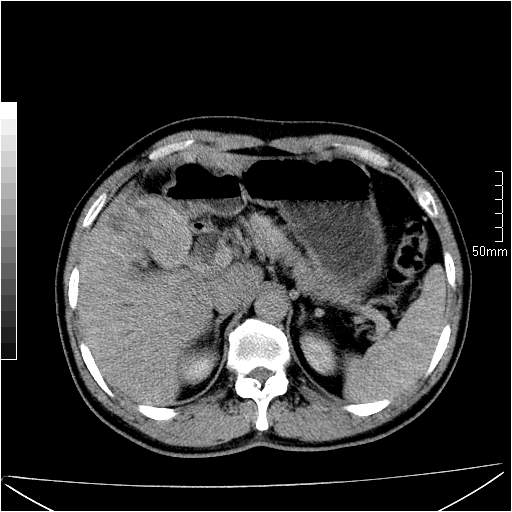

男性,54岁,皮肤黄染,搔痒一周余.b超示肝左叶回声异常.初步诊断1胆总管下段结石2胆囊结石伴慢性胆囊炎请各位战友帮忙看一下肝脏多发低密度如何解释恰当.增强效果不是很好.请大家见谅.

胆总管及肝内胆管扩张,考虑是结石!但,肝内的低密度区增强不明,可能是肝ca,因为肝ca在增强时呈快进快出.另年胆总管扩张原因,可以考虑一下是不是,胆管ca.再次要考虑肝内的低密度是否为海绵状血管瘤所致!

首先,胆总管下端结石梗阻伴肝内胆管扩张可确定。

其次,增强动脉期肝静脉显影,肝实质密度不均。——此为右心功能不全引起肝淤血的表现。

另外,肝八段低密度占位,呈多灶性,考虑肝脓肿或肝癌可能,(图像质量欠佳)建议进一步检查。

既然做了增强,为什么光提供延时期片子,肝动静脉期肝右叶前下段病灶增强如何?另外胆囊壁增厚,欠规整,内密度不均,与肝右叶病灶分界不清,增强表现怎样?肝内胆管轻度扩张,胆总管扩张,但未见明显结石影,也应提供增强早期图像才好鉴别扩张原因。片子较清,但不够完整,暂考虑1.胆囊癌肝局部浸润,或肝癌胆囊侵犯,2.胆总管下端或胰头钩突部占位。总之本人看不明白,请高手画图指示,先谢了!

由于胆囊窝内结构显示不清,肝脏病灶又邻近胆囊窝首先考虑胆囊癌肝受侵犯。而后因肝脏病灶强化有渐进改变,且相邻胆管扩张,故考虑肝胆管细胞癌待排。

左肝胆管细胞癌。

胆总管下端结石。